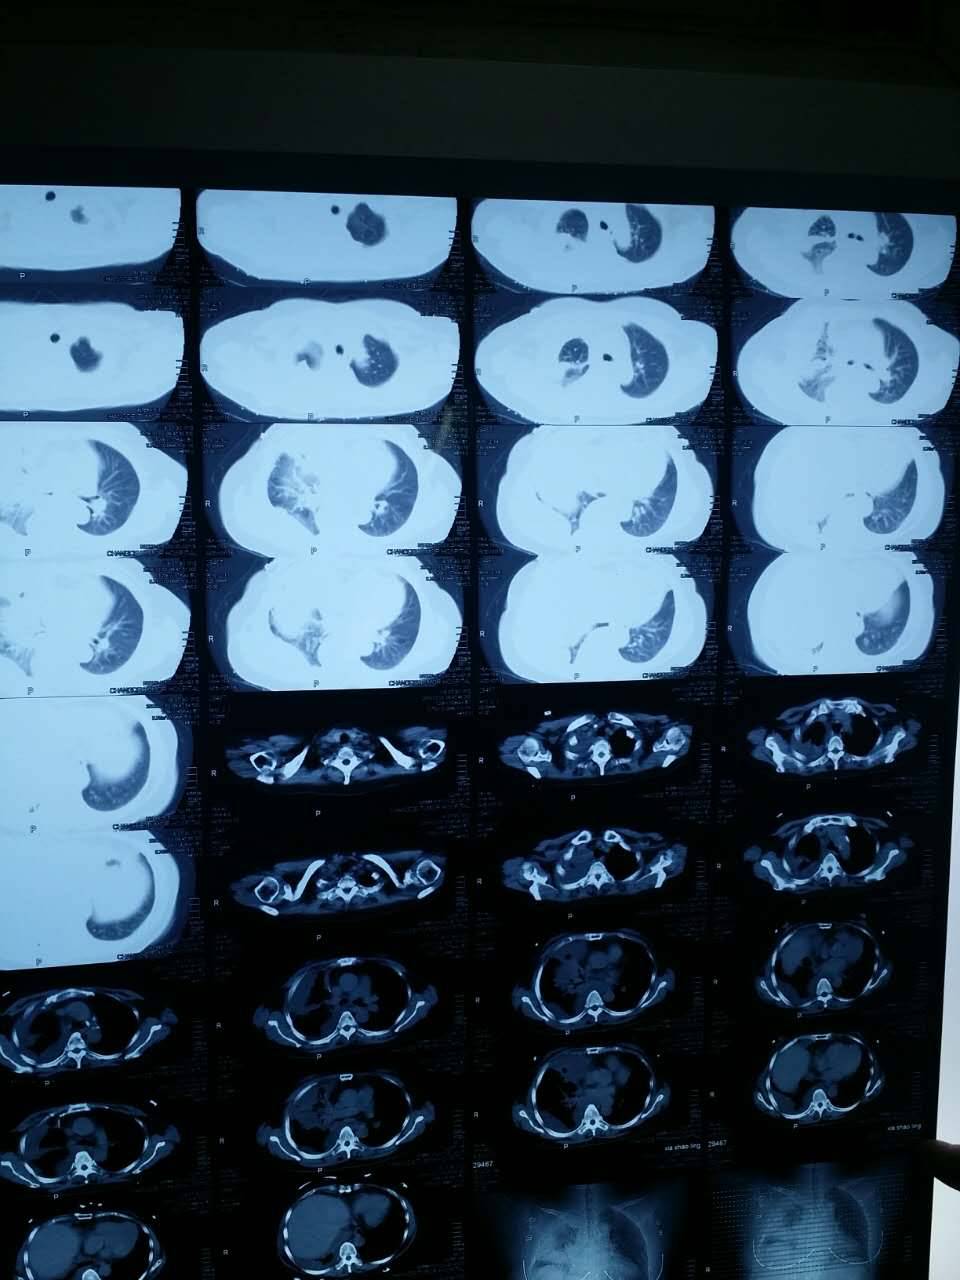

亲们,我妈21突变,今年3月开始吃易瑞沙,胸水减少了,咳嗽少了,最近复查胸水多了,咳嗽厉害了,但是我妈没有脑转,而且我妈的cea之前400多,现在还是三百多,换特罗凯行吗?请问吃特的最佳时间是什么时候?需要吃什么保健品保护内脏吗?